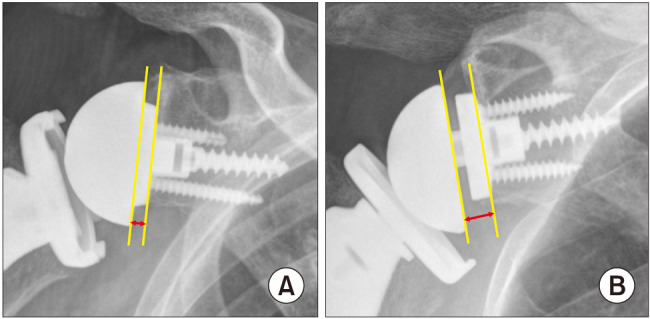

Methods: This prospective study enrolled 120 patients who underwent RSA for a symptomatic irreparable massive rotator cuff tear, cuff tear arthropathy, or primary osteoarthritis with a full-thickness rotator cuff tear. Patients were randomly allocated 2:1 to receive an Asian-type RSA implant (group I) or conventional RSA implant (group II). All patients underwent plain radiography to evaluate acromiohumeral distance, acromion-deltoid tuberosity distance, lateral humeral offset, and center of rotation distance. Postoperative 1-year computed tomography (CT) scans were obtained for all patients to evaluate the position of peg screws and baseplates and the presence of scapular notching. Clinical outcomes were evaluated using American Shoulder Elbow Surgeons (ASES) score, Constant score, and active range of motion.

Results: Finally, 112 patients (80 in group I and 32 in group II) were included in this study. The mean patient age was 74.0 ± 5.5 years, and the mean patient height was 154.6 ± 8.1 cm. At the last visit, clinical scores and active range of motion significantly improved in both groups; however, the improvements did not differ significantly between the 2 groups. On the postoperative 1-year CT scan, the glenoid baseplate was more anteriorly placed in group II than in group I. The supero-inferior position of the glenoid baseplate did not significantly differ between the 2 groups. Other radiological parameters obtained through plain radiography showed no significant differences between the 2 groups. No differences were found in scapular notching (p = 0.999) and acromial stress fracture (p = 0.872) between the 2 groups.